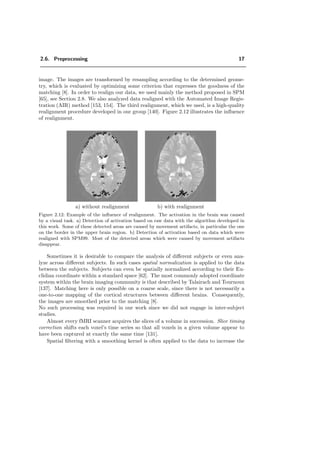

realignment procedure developed in our group [140]. Figure 2.12 illustrates the influence

of realignment.

a) without realignment b) with realignment

Figure 2.12: Example of the influence of realignment. The activation in the brain was caused

by a visual task. a) Detection of activation based on raw data with the algorithm developed in

this work. Some of these detected areas are caused by movement artifacts, in particular the one

on the border in the upper brain region. b) Detection of activation based on data which were

realigned with SPM99. Most of the detected areas which were caused by movement artifacts

disappear.